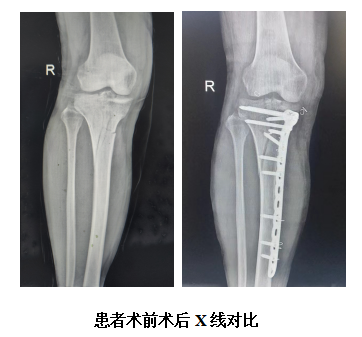

近日,泰安市中心医院分院骨外科团队成功为一名膝关节骨折患者行膝关节镜下“微创小切口右膝关节、胫骨骨折切开复位内固定术”,术程短、创伤小、出血少,目前,患者骨折部位逐渐好转,即将出院。

为了让患者更好的恢复膝关节功能,避免小腿留下明显疤痕对以后的生活造成影响,骨外科团队在对患者情况进行全面评估后,决定在膝关节镜下实施“微创小切口右膝关节、胫骨骨折切开复位内固定术”,对事故中造成的骨折错位进行复位固定,同时探查关节韧带是否损伤并修补。术中,麻醉科、骨外科密切配合,在患者膝前内侧切开了一个约5cm的纵行切口,使用10孔T形钢板在皮下潜行后定位支撑,于胫骨远端依次打入3枚锁定螺钉,在关节镜下对骨折部位进行复位固定,并使用锚钉复位固定撕脱骨折的前交叉韧带。

骨外科主任国华介绍,如采用传统的开放手术治疗该患者,切口最小要有25cm,且对骨膜剥离广,影响骨折愈合,并会留下较大的疤痕,影响美观。而用微创方法进行复位固定,隐形进入关节,潜行固定骨折,不仅能达到复位牢固固定的效果,且创伤小,对骨折端干扰少,不影响骨折愈合,术后手术部位疼痛少,疤痕小,对外观影响小,住院时间和术后固定时间都可缩短,能尽早进行关节功能锻炼,对患者后期康复有很大的帮助。